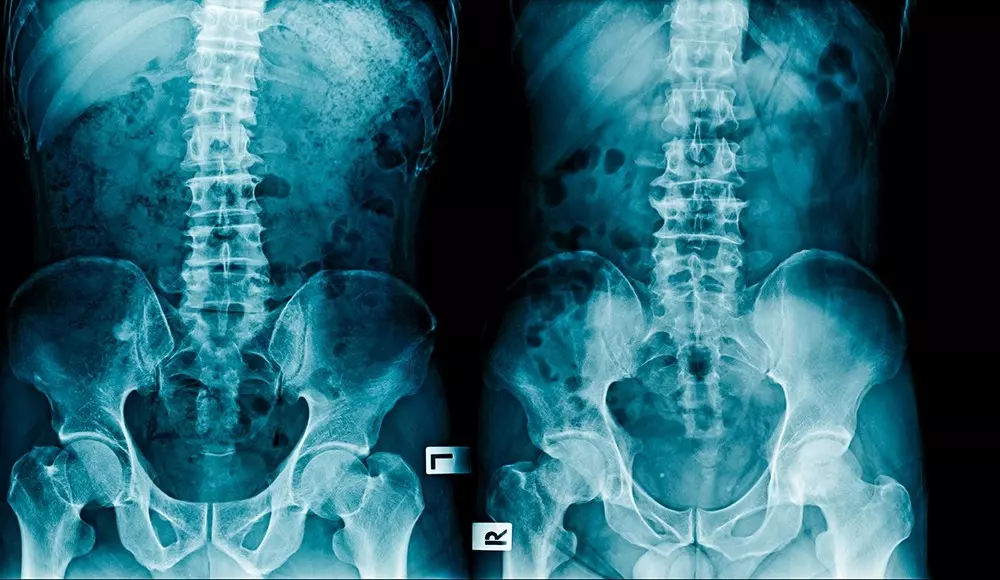

Osteoporoza

Autorzy opracowania wskazują, że osteoporoza jest obecnie problemem medycznym, społecznym oraz ekonomicznym. W Polsce niestety brakuje powszechnie dostępnych programów zapobiegania upadkom osób starszych oraz właściwego dostępu do lekowych programów leczenia oraz profilaktyki osteoporozy.